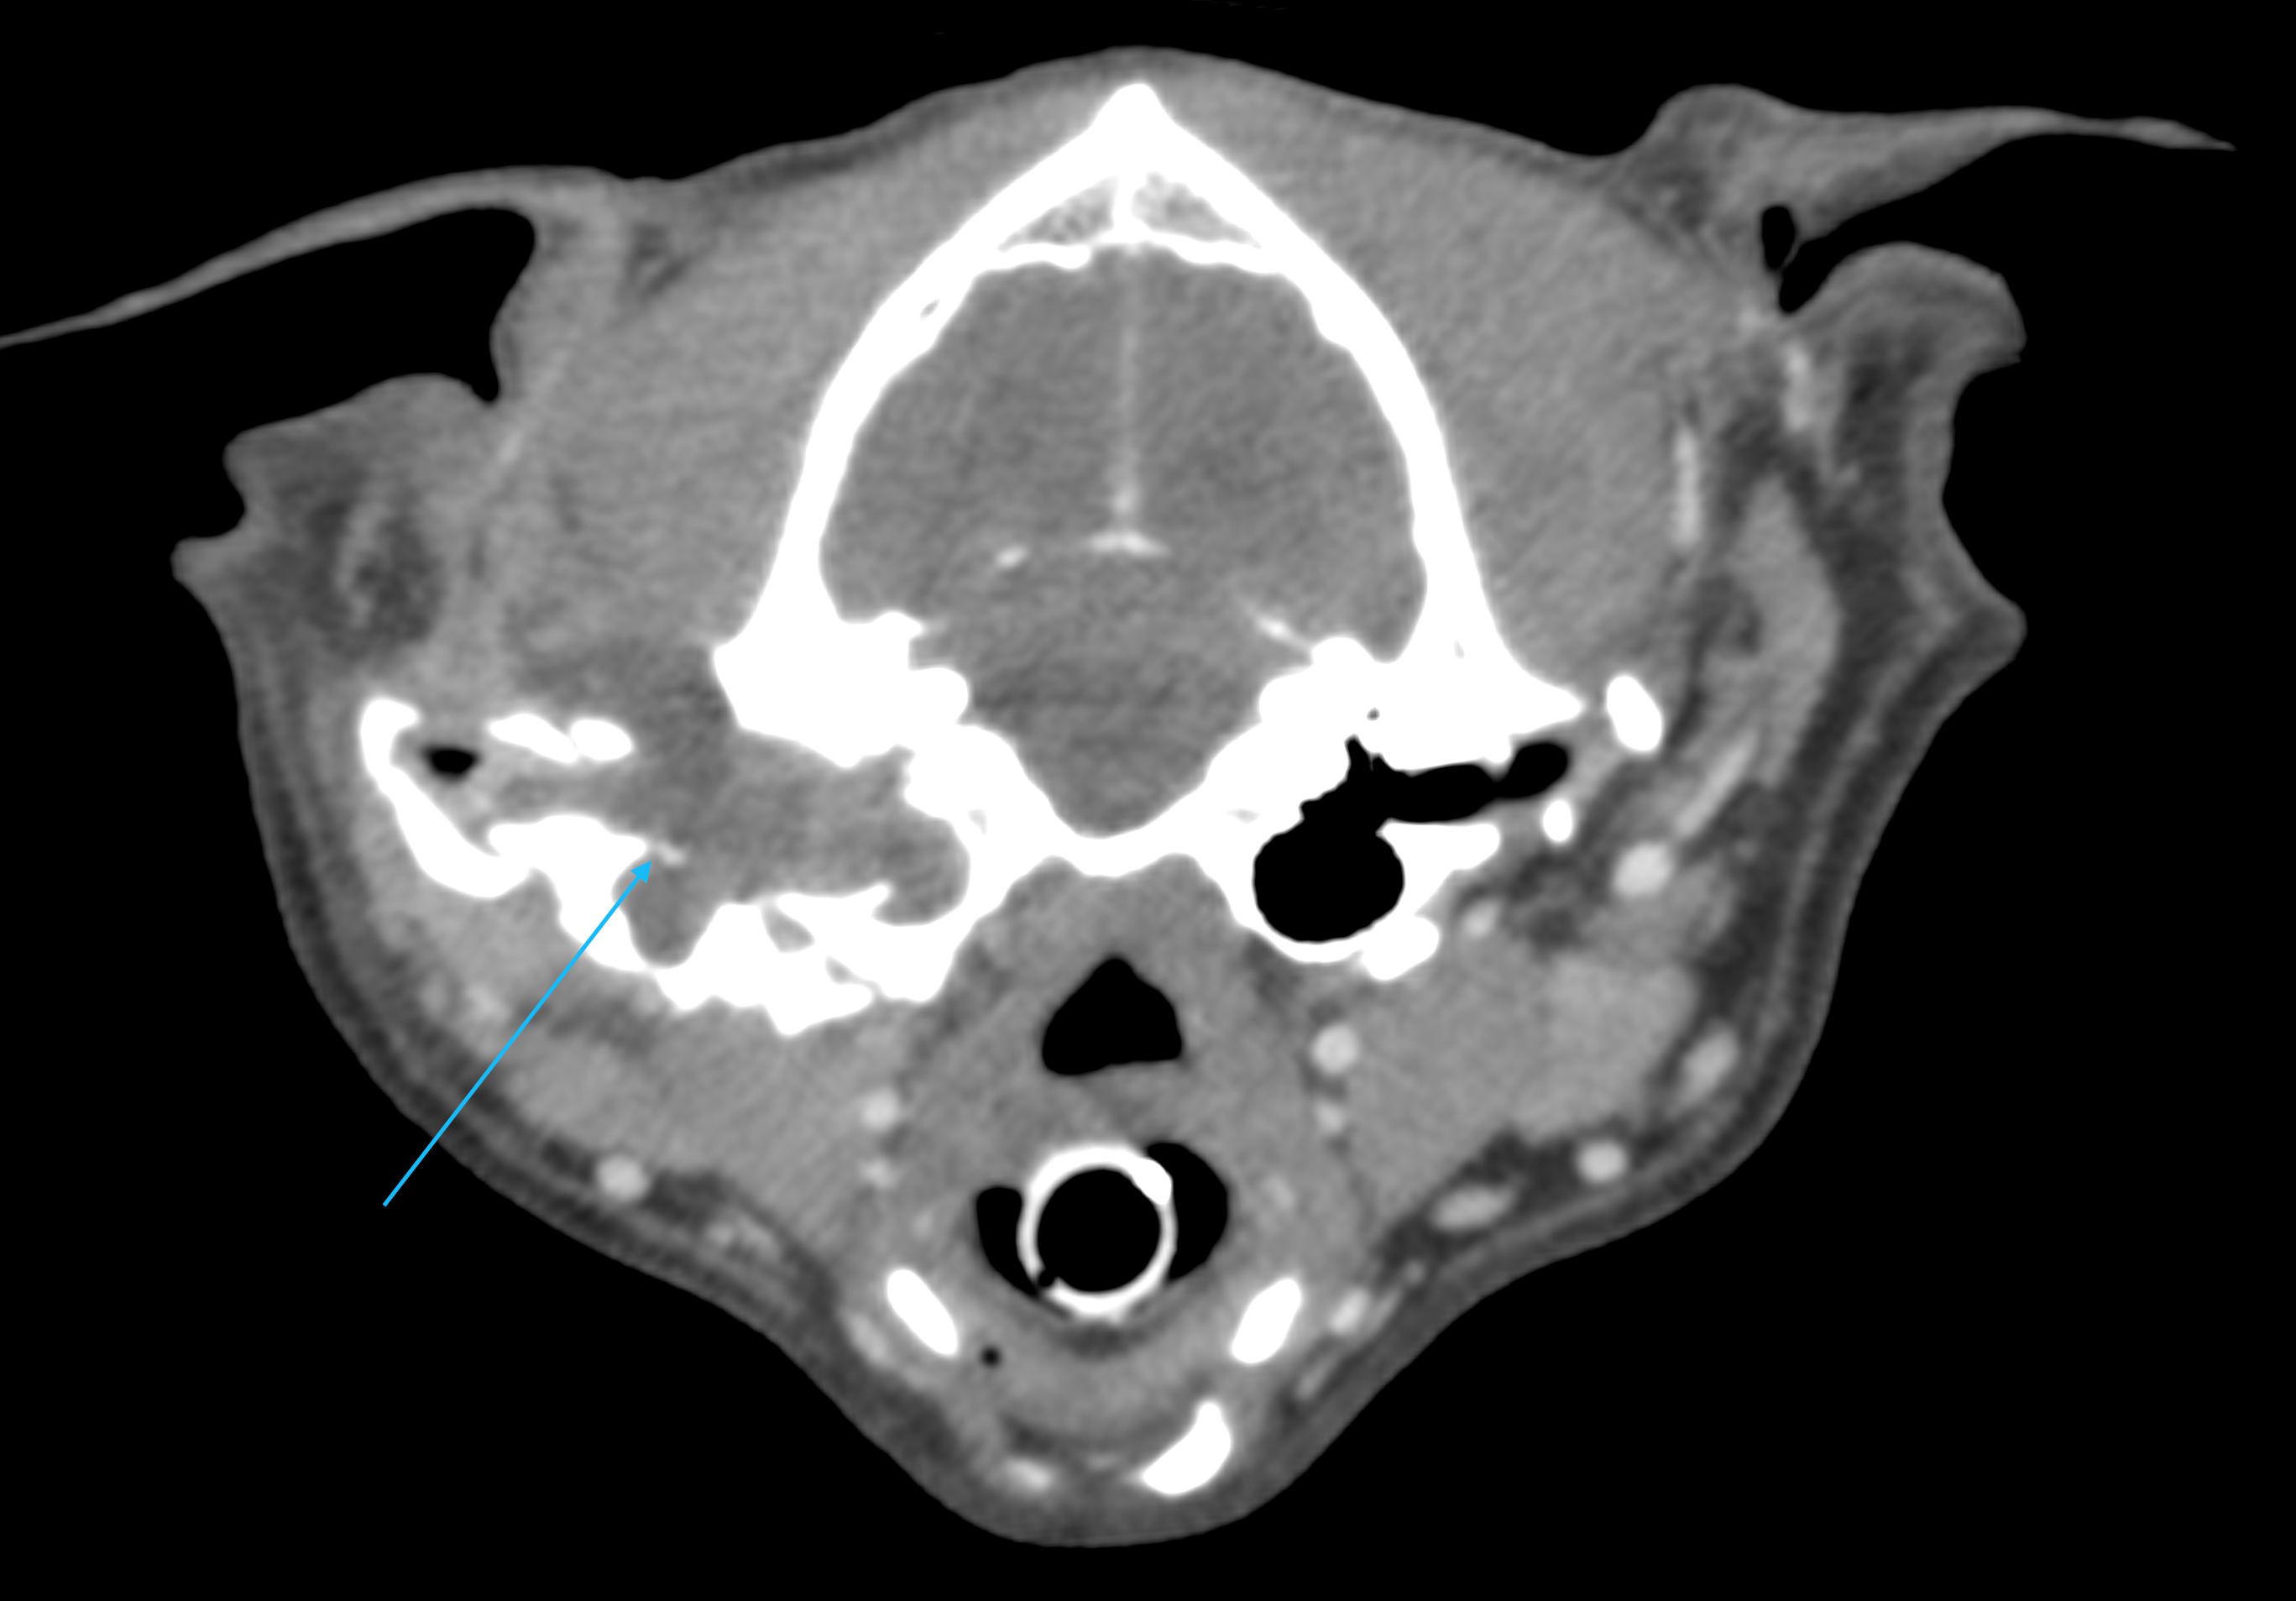

こんにちは、獣医師の依田です。 今回は、耳の根元の腫れで来院したわんちゃんの紹介です。 飼い主様が数日前から耳…]]>

こんにちは、獣医師の依田です。 今回は、耳の根元の腫れで来院したわんちゃんの紹介です。 飼い主様が数日前から耳…]]>